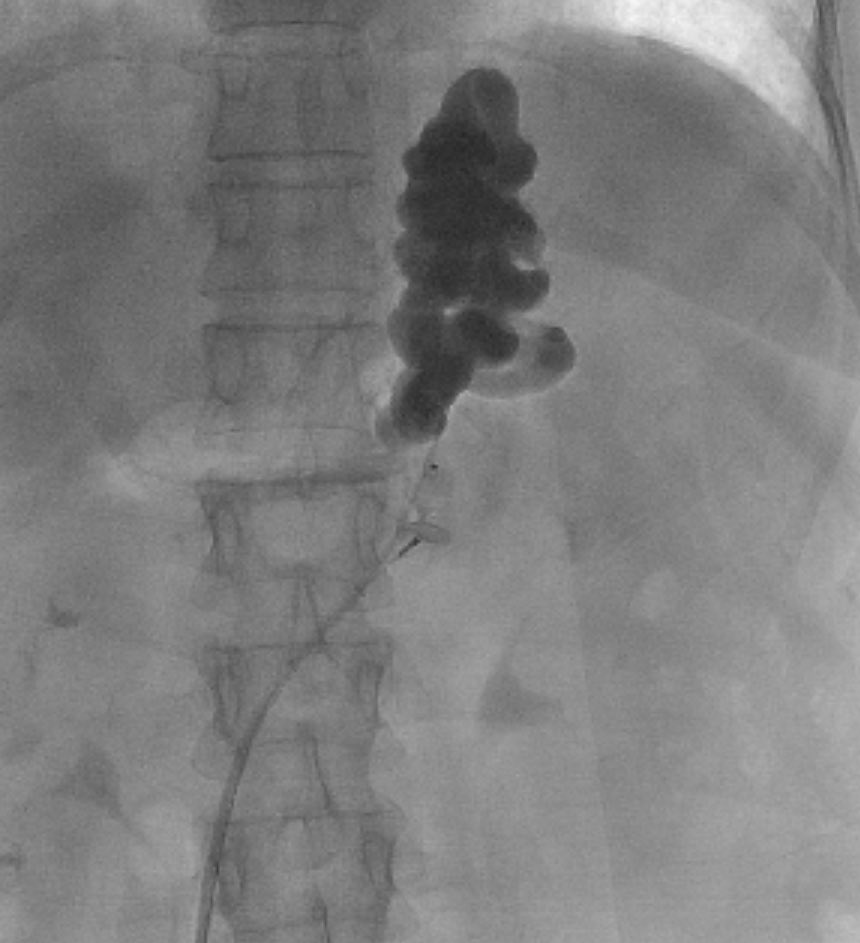

#PARTO

علاج دوالي المعده المسببه للنزيف المعوي الحاد بسبب ارتفاع ضغط الوريد البابي في الكبد عن طريق #القسطره و #الأشعه_التداخليه

العربية